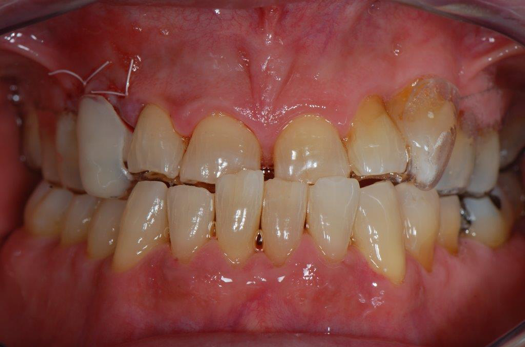

Fig 1. Preoperative surgery.

Figure 1

A patient presented to the dental practice with multiple root fractures, recurrent caries, and a need for significant crown-lengthening procedures, endodontic therapy, post and cores, and long-term restorations. The patient considered the entire volume of therapy and was not interested in undergoing treatment with less than a satisfactory long-term prognosis. The patient was given two dental-implant options and chose to move forward with ceramic dental implants.

Figure 1 and Figure 2 depict the preoperative image and subsequent removal of three posterior teeth, immediate placement of zirconia-oxide ceramic dental implants, and soft-tissue augmentation with platelet-rich fibrin (PRF) to enhance the soft-tissue architecture surrounding the ceramic implants. The teeth were removed atraumatically and without suture placement. Because the implants were one-piece in stature (the abutment was incorporated into the implant), the recommendation was to splint the multiple units to minimize the lateral forces from mastication, swallowing, and tongue movement.